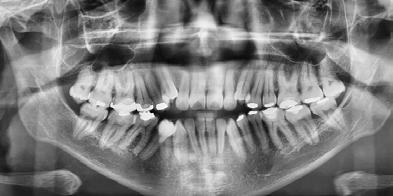

En la radiografía panorámica (Figura 8) se observan 32 dientes presentes

en boca, con la rehabilitación de los órganos dentarios por oclusal, con obturaciones de amalgamas, e incrustaciones, y divergencias radiculares inadecuadas.

Figura 7. Radiografía lateral de cráneo. Figura 8. Radiografía panorámica.

En la radiografía panorámica se ven 24 órganos dentales (Figura 12) después de realizada la cirugía osteotomía Lefort I maxilar de avance y una mentoplastía; las cuatro placas de fijación con sus respectivos microtornillos en el maxilar líneas de color rojo, la fijación con alambre quirúrgico de acero inoxidable señalados azules.